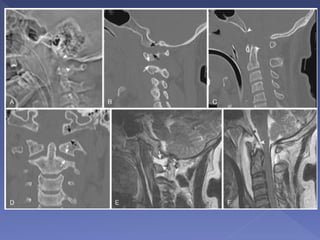

Atlantoaxial rotatory subluxation associated

with left lateral mass of C1 fracture

A: shows rotation of C1 to the right.

B: fracture of the left lateral mass of C1

C: asymmetry of the lateral atlanto-dental

spaces (black arrows) and a difference in the

atlantoaxial joint spaces (white arrows)

secondary to rotational malalignment.

Increased transverse diameter of the left lateral

mass of C1 (black dot) and truncated

appearance on the right (white dot) indicate

rotation of C1 to the right.